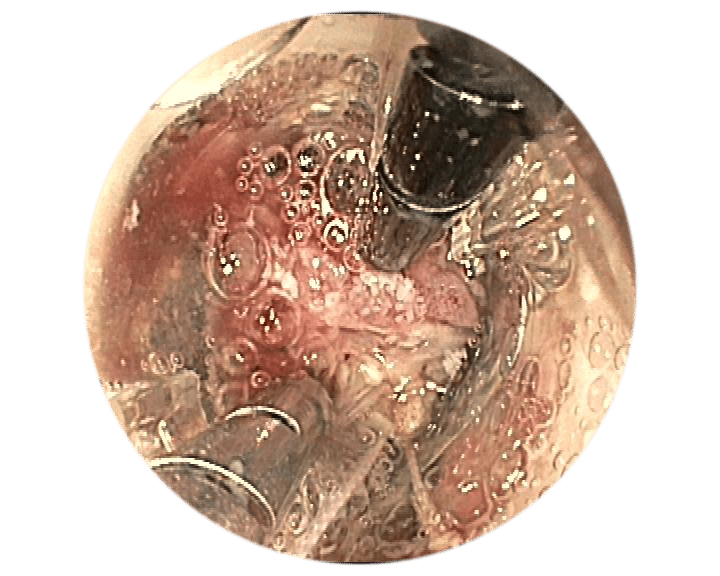

Anvisieren der Applikationsstelle.

Einführen des Führungsdrahts in den äußeren BARS® Arbeitskanal und Vorlegen in der Anastomose.

Einführen der Anker in den Endoskop-Arbeitskanal und den inneren BARS® Arbeitskanal.

Überkreuztes Platzieren der Anker im vorbereiteten Zielgewebe.

Platzieren des Kalibrierballons in der Anastomose. Schrittweises Einziehen des Gewebes in die BARS® Applikationskappe, mit abwechselnden Zugbewegungen.

Sicherstellen, dass das Gewebe symmetrisch in der Kappe positioniert ist. Platzieren des BARS® Clips durch Drehen des Handrads.

Zurückziehen der Instrumente und Inspektion der Clip-Applikationsstelle.

1Quelle: Dr. med. M. Kandler, Städtisches Klinikum Dresden, Deutschland